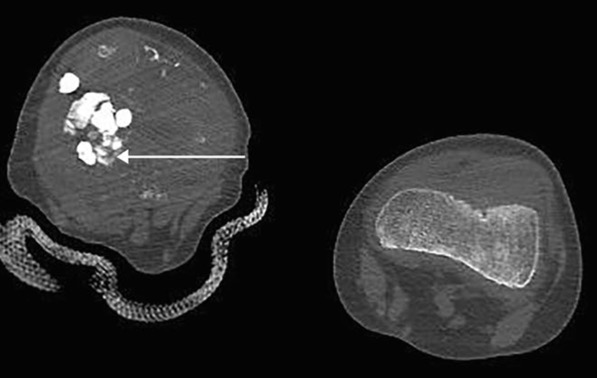

calcinose tumorale

Affection rare

Dépôt de masses de sels de calcium dans les tissus mous, souvent près des articulations

Ressemblent à des tumeurs mais NON cancéreuses

=> gêne, douleur, limitation